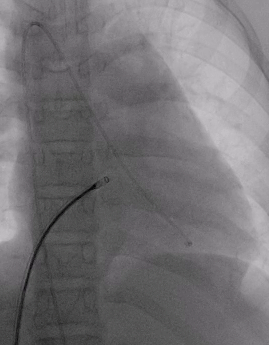

术前造影:室间隔缺损处造影,造影显示有膜部瘤形成,测量缺损大小,左侧基底大小10.8mm,右侧分流口2处,分流大小约2mm。

室间隔缺损介入封堵

根据术前测量和术中造影结果,选择MemoSorb全降解封堵器ABFDQ-Ⅱ08,配合8F可降解封堵器介入输送系统进行封堵。

建立输送轨道

飘导丝法导丝过室间隔缺损

圈套器抓捕导丝

送入8F输送鞘

改变输送鞘方向

使输送鞘朝向心尖

展开左右盘面

左盘展开

右盘展开并造影

基本无残余分流